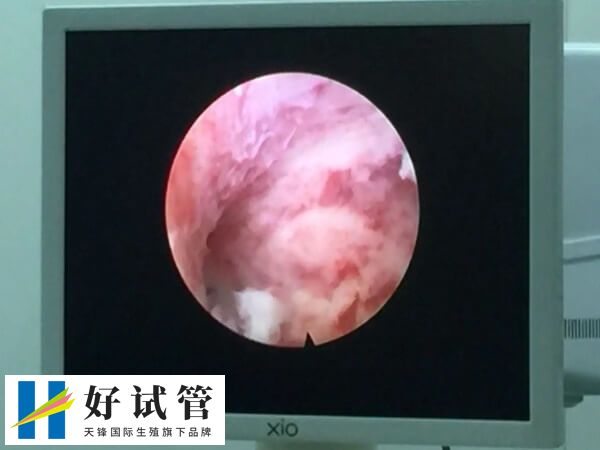

打完降调后做完宫腔镜的患者,如果只是进行简单的宫腔镜检查,检查后没有发现有明显的器质性疾病,并且也没有实施手术治疗,那么对子宫的伤害是比较小的,一般检查结束后子宫可很快恢复正常状态。

患者在打降调针之后,如果做宫腔镜检查的同时发现有子宫粘膜下肌瘤、子宫内膜息肉等良性疾病,那么可能会进行病灶切除手术,这时可能会对子宫内膜造成一定的损害,但如果患者已经去除且预后良好的情况下,可能在术后1-3个月左右就可以进行胚胎移植了。

一般患者在打完降调月经干净后的第3-7天内进行宫腔镜检查,如果宫腔镜没有发现任何问题(如子宫内膜息肉、宫腔粘连、子宫内膜炎等),并且宫腔镜检查也没有对身体和子宫内膜造成伤害,那么术后月经来潮就可以进入试管婴儿的移植周期,反之则可能需要根据具体情况调整移植时间。